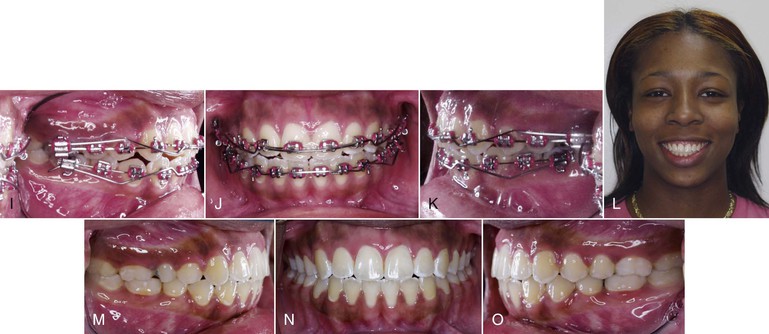

Patients with tongue thrusting can be treated effectively in the same manner as that used for patients who suck on a thumb or finger (Fig. 9-9), although different appliances, such as the habit appliance with lingual spurs or cribs (Fig. 9-10), have been suggested. In one study,62 immediately after crib placement the tip of the tongue was positioned posteriorly during all stages of deglutition. Additionally, the anterior and middle parts of the dorsum of the tongue were at a lower position, reflecting a compensatory functional change for bolus propulsion and airway protection. However, no significant change occurred in the posterior part of the dorsum. Taslan et al.63 reported a decrease in resting tongue pressure and swallowing pressure from 21 g/cm2 to 13 g/cm2 and 216 g/cm2 to 143 g/cm2, respectively, after 10 months of tongue crib therapy in patients with anterior open bite. This decrease in tongue pressure at rest and swallowing pressure after crib therapy was suggestive of tongue adaptation in response to the altered environmental changes. This altered tongue posture aided in the correction of an anterior open bite through an increase in overbite of 3.6-mm. The increase in overbite was attained by lingual inclination of the maxillary and mandibular incisors by 4 degrees each and by extrusion of 1.4-mm and 1-mm, respectively.64

Figure 9-9 Female patient, age 18, with a tongue thrust. A–C, Extraoral views. On smile, only 50% of the incisors are displayed and an anterior tongue posture is evident. A reverse smile arc is consistent with the tongue thrusting habit. D–F, Intraoral views show a 3-mm anterior open bite with divergent occlusal planes from the first premolars. G, Lateral cephalogram shows a dental anterior open bite with dentoalveolar protrusion. H, Habit appliance with first and second molar bands and anterior loop design close to the palate. I, Intraoral view of the cemented habit appliance. J, Brackets are placed after 6 months of exclusive treatment with the habit appliance. Fifty percent of the negative open bite self-corrected. K–M, Extraoral views after treatment. A positive smile arc was obtained, with approximately 90% incisor show on smile. N–P, Adequate overbite was achieved with a good Class I relationship. Q, Final lateral cephalogram shows the overbite correction. R, General superimposition shows no maxillary or mandibular growth. Controlled lingual tipping of the upper and lower incisors reduced the dentoalveolar protrusion and anterior open bite. S, Regional maxillary and mandibular superimpositions show the same dental movements described previously (pre-treatment age, 18.8 years; post-treatment age, 21.5 years).